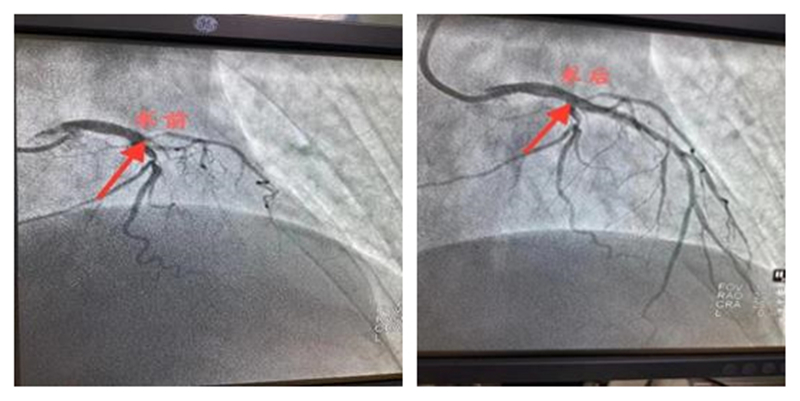

术中和预判的一样,前降支开口100%闭塞,经过家属同意后,迅速开通了闭塞的前降支,于左主干-前降支病变处植入支架1枚,患者终于转危为安。